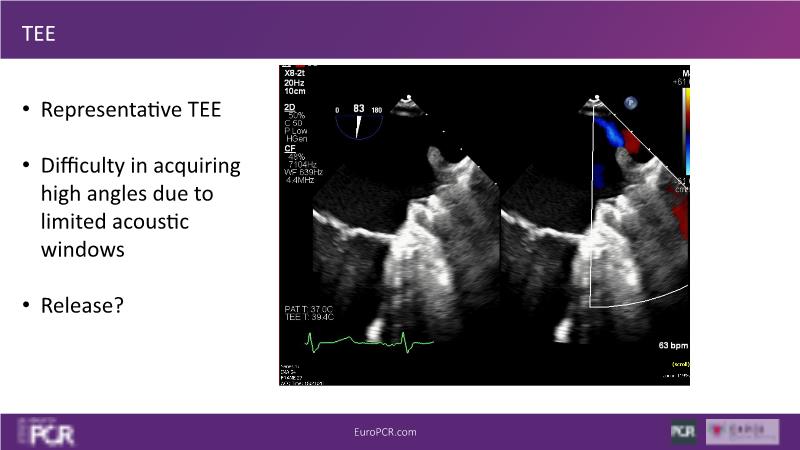

Explore this session to discover the latest innovations in interventional cardiology images, including the benefits of artificial intelligence and angio-CT in PCI/SHD procedures. Learn about Alphenix Evolve and the initial experiences with AI imaging in daily cathlab practice, alongside intraprocedural angio-CT guided LAAO, and engage in discussions on meaningful tools that can transform patient care.